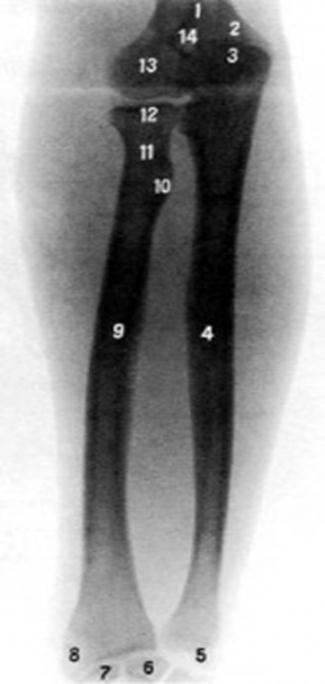

S: Цифра 9 указывает на …

+:radius

-:ulna

I:

S: Цифра 4 указывает на …

-:radius

+:ulna

S: На рентгеновском снимке изображен articulatio ### (латинский язык).

+:cubiti

+:Сubiti